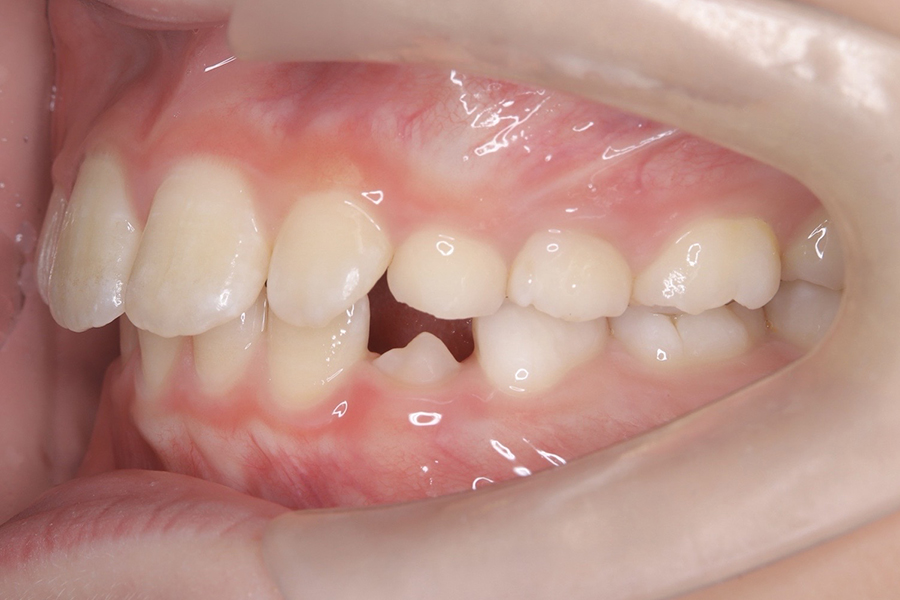

FDT症例② S.Hくん(10)

治療前

相談内容 |

うつ伏せ寝、口呼吸が気になる 歯並びの悪さ |

カウンセリング・診断結果 |

口呼吸、低位舌、上下顎劣成 |

行った治療内容 |

FDT(筋機能矯正治療/マイオブレース治療) |

治癒期間 |

2024.8.31〜 |

費用 |

385,000円(税込) |

治療リスクについて |

・お子様・保護者の協力が必要。 |

担当者からのコメント |

頑張り屋さんで真面目なHくん。正面から見ると一見綺麗ですが、横から見た時の前歯の出っ張りや永久歯の生えるスペースがないためFDTを始めました。 |